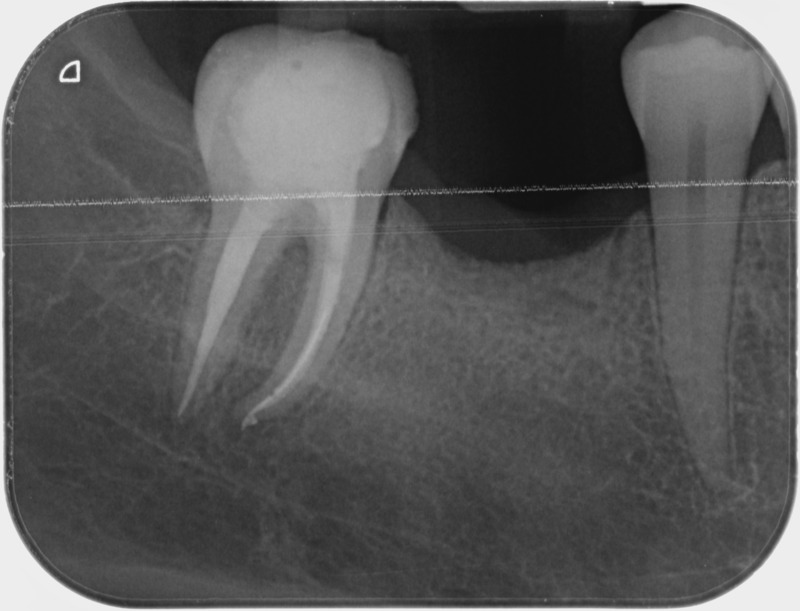

• Traitement endodontique : Sous anesthésie locale et à travers la protection d’un champ opératoire nous accédons à la pulpe de la dent à soigner, puis aux canaux de ses racines que nous devons désinfecter. Ce soin nécessite l’élimination complète de la source de contamination (souvent la carie) parfois sous une ancienne reconstitution ou une couronne qu’il faut alors retirer. Une fois le nettoyage et la mise en forme des canaux réalisés, nous les obturons de façon hermétique avec un ciment et un matériau thermoplastique appelé Gutta Percha. Ceci afin d’empêcher une nouvelle prolifération bactérienne et d’assurer le maintien de la dent dans ses structures de soutien (ligament parodontal et os alvéolaire). L’ouverture effectuée au centre de la dent sera d’abord refermée avec un pansement provisoire avant d’envisager ensemble la reconstitution d’usage : un composite, un inlay-onlay ou une couronne.

Avant